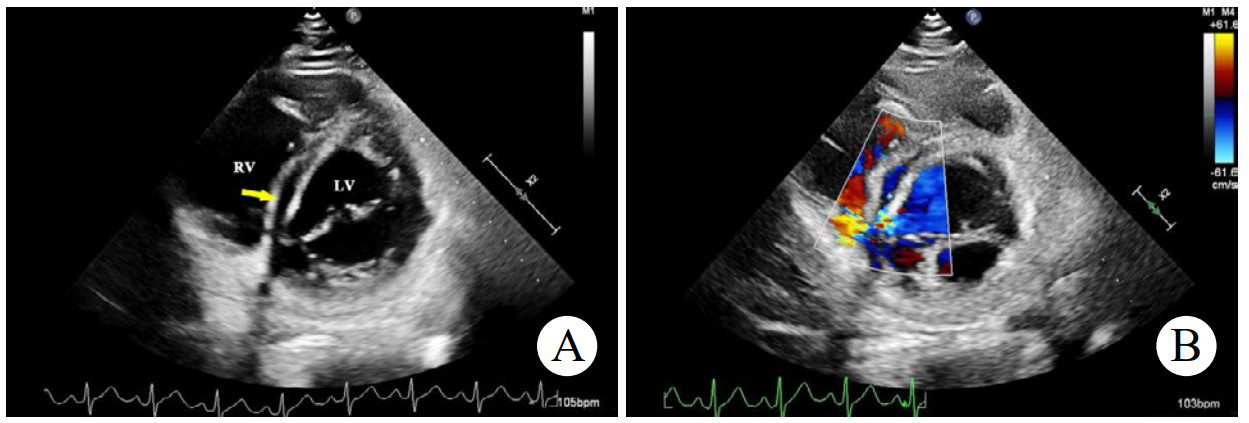

术前心脏计算机断层扫描血管造影(computed tomographyangiography, CTA)检查未能明确诊断右乏氏窦瘤破裂(图 4),这给临床医生带来一定困惑。经急诊超声心动图检查及临床医生全面评估后行右乏氏窦瘤破裂修复术和主动脉瓣成形术。取适当大小的牛心包补片,间断褥式缝合修补破口及室间隔夹层,并行主动脉瓣成形术。术中经食道超声心动图显示窦瘤破裂修补完好,分流消失,主动脉瓣瓣叶开闭良好,反流消失。术后1个月复查,二维超声心动图显示主动脉短轴切面:右乏氏窦瘤破裂修补处回声增强,连续性好;CDFI:该处分流消失。主动脉瓣瓣叶开闭正常。胸骨旁四腔心切面显示如上(图 5),室间隔回声稍不均质,室间隔夹层动脉瘤完全塌陷,未见夹层动脉瘤显示。

| 注:A为2D超声显示胸骨旁四腔心切面右乏氏窦瘤破裂修补处(黄色箭头)回声增强,连续性好;B为CDFI显示该处分流消失 图 5 2D及CDFI显示右乏氏窦瘤破裂修复术和主动脉瓣成形术后表现 |